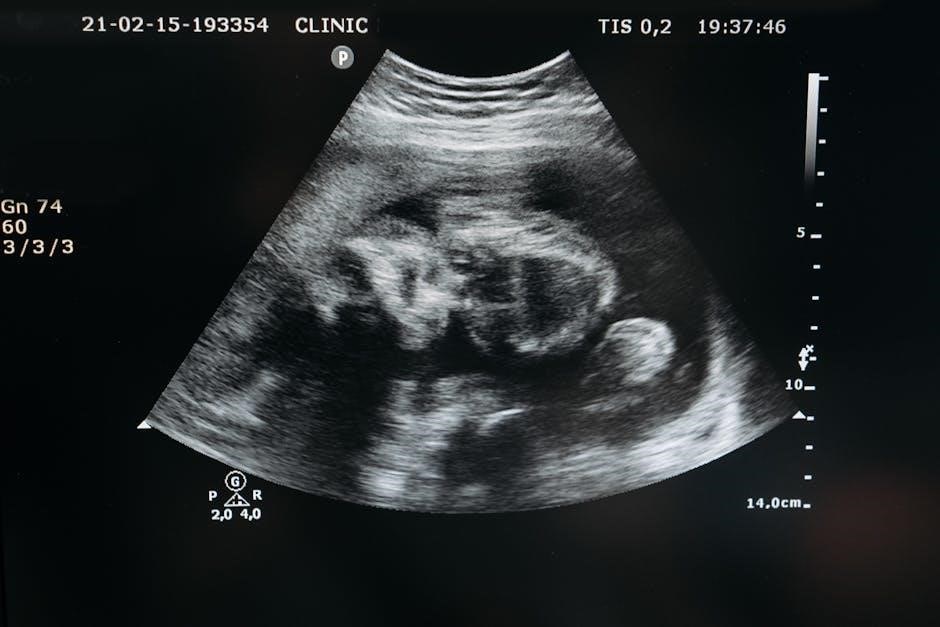

Ultrasound-guided procedures utilize real-time imaging to precisely guide instruments during various medical interventions. These techniques encompass a broad spectrum‚ including peripheral intravenous access (UGPIV)‚ liver biopsies‚ fine-needle aspirations‚ and thoracentesis.

Unlike traditional methods‚ ultrasound provides visualization of underlying structures‚ allowing healthcare professionals to navigate with increased accuracy. This minimizes the risk of complications and enhances diagnostic yield‚ ultimately improving patient outcomes. The development stems from advancements in optical and fluoroscopic imaging‚ paving the way for minimally invasive approaches.

Real-time imaging is the cornerstone of ultrasound-guided procedures‚ allowing healthcare professionals to visualize anatomy and guide instruments dynamically. This capability is crucial for procedures like thoracentesis and fine-needle aspiration‚ ensuring accurate needle placement and minimizing risk.

The continuous visual feedback provided by real-time ultrasound enhances precision‚ avoids critical structures‚ and confirms successful tissue sampling‚ ultimately improving patient safety and procedural outcomes across diverse clinical applications.